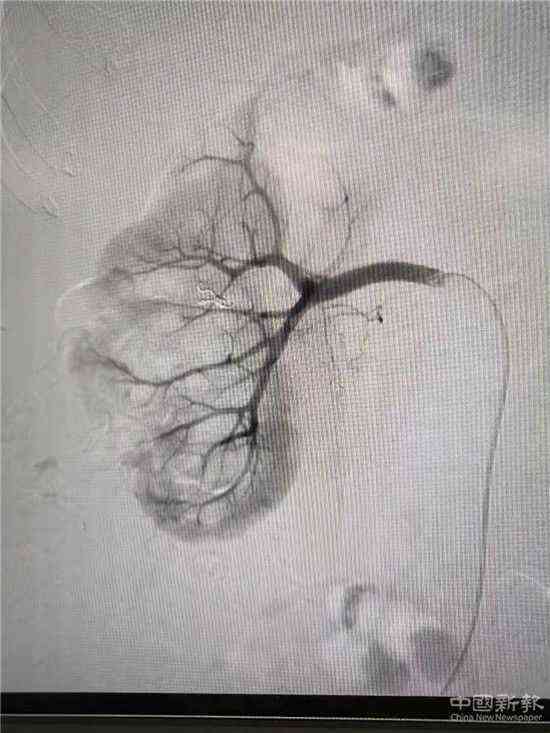

栓塞后造影圖(已止血)

家住湖南省郴州市嘉禾縣廣發(fā)鎮(zhèn)的鄧大媽,因患巨大腎結(jié)石進(jìn)行了“經(jīng)皮腎鏡取石術(shù)”,術(shù)后第3天出現(xiàn)大量鮮紅色血尿。經(jīng)過增強(qiáng)CT檢查,考慮為“腎穿刺口處動(dòng)脈出血”,醫(yī)院介入血管外科團(tuán)隊(duì)立即為患者在DSA下行“微創(chuàng)介入右腎出血?jiǎng)用}栓塞術(shù)”,術(shù)后出血立刻停止,尿液由紅色轉(zhuǎn)為正常顏色。